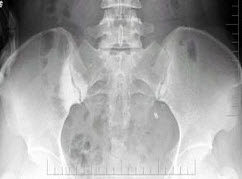

10、单项选择题

男,根据其正常骨盆影像图像,判断其最可能的年龄()

A.1岁左右

B.4岁左右

C.7岁左右

D.10岁左右

E.13岁左右